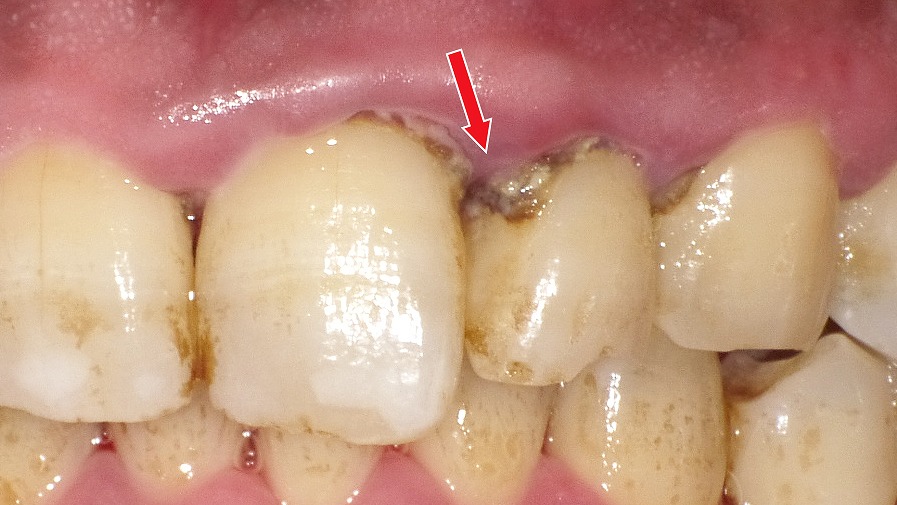

赤矢印が示すように、歯と歯の間(コンタクト部)の初期虫歯は、肉眼ではほとんど確認できません。レントゲンを撮影することで、エナメル質内部の透過像として虫歯を早期に発見できます。見た目に穴がなくても進行している場合があるため、定期的なレントゲン検査は非常に有効です。